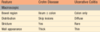

Which dz’s have defect of only transepithelial transport

carcionoid syndrome

Abetalipoproteinemia